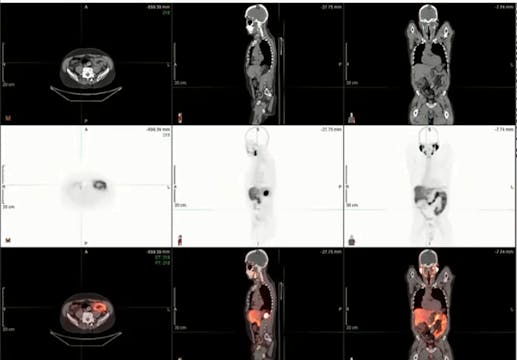

prostate cancer, local recurrence, PSA, ADT, fistula, cardiac comorbidity, brachytherapy, external beam radiation, high risk

Gleason 6, Low Risk, Watchful waiting, SBRT toxicity, SIB, bladder cancer, low pelvis, hypofractionation, defining target, PSMA, prostate cancer, pT3aN0M0, rpT3acN1M0

IGRT, SBRT, fractionation, intratreatment, brachytherapy, urology, ADT, PSMA, PSA